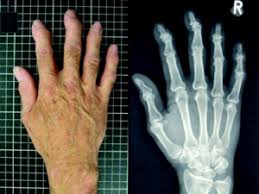

Håndleddsbrudd er en av de vanligste bruddtypene, og er brudd like ved eller i håndleddet. Brudd i håndledd, operasjon med innvendig plate, mo i rana. Brudd i finger og hånd er hyppig forekommende skader som ofte kan behandles uten operasjon, men feilstillinger i fingre tolereres dårlig og kan kreve kirurgiske tiltak. Vanligvis behandles dette uten operasjon med gradvis økende. Diagnostisering av brudd i underarm. Dermed ble det brudd, og oppgjøret går til megling. Det er et brudd i ankelen hennes. Brudd eller brott kan bety: